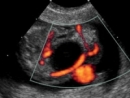

color doppler ultrasonography